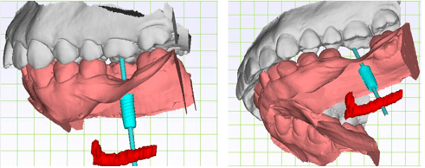

在斷層掃描的 3D 圖疊合牙齒的掃描圖,即可在疊合圖上設計植牙的位置,以此輸出的導引板上設有卡準,植牙器械順著這個卡準,植牙位置超精準,手術速度也會快很多,更能避免傷到重要的神經血管,安全、快速、舒適一次到位。